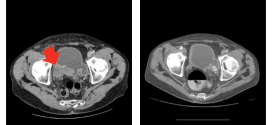

Leer MásTUMOR VESICAL MACROSCÓPICAMENTE (masa extravesical)

El tumor vesical macroscópicamente (masa extravesical) (T3B). Durante los primeros años de vida de una persona, las células normales se dividen más rápidamente para permitir el crecimiento. El cuerpo está compuesto por billones de células vivas. Las células normales del cuerpo crecen, se dividen formando nuevas células y mueren de manera ordenada. Una vez que se llega a la edad …

El tumor vesical microscópicamente (T3a). Tumor maligno en general. La orina es un líquido formado por agua y sustancias de desecho del organismo. Esta se produce por el filtrado de la sangre en los riñones. A través de unos tubos largos y finos, denominados uréteres, la orina llega a la vejiga y se almacena en ella. La orina, una vez …

El tumor vesical que invade (próstata, útero o vagina (T4a). Tumor maligno en general. Publicado en: binipatia.com Escrito por: Salvador Gregori y Daniel Lynch Etiquetas: salud verdadera, resultados Resumiendo: La vejiga urinaria es un órgano hueco musculo membranoso que forma parte del tracto urinario y que recibe la orina de los uréteres y la expulsa a través de la uretra al exterior …